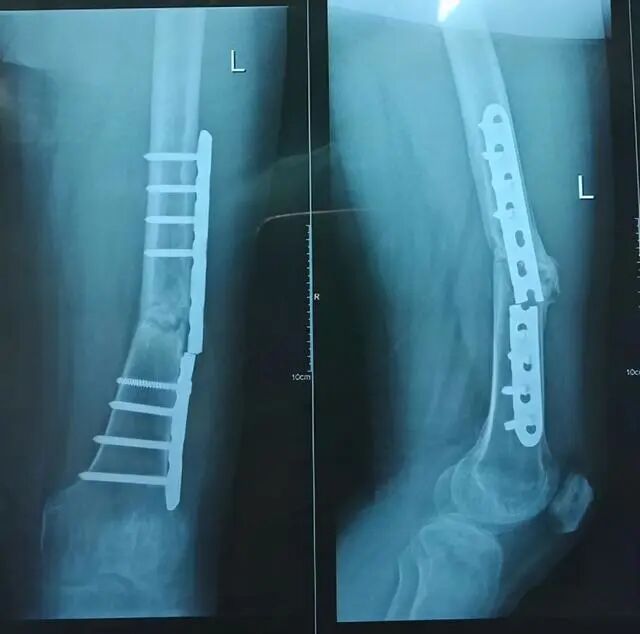

遇到了骨折患者术后钢板断裂,螺钉松动。面对这种情况,大多数患者会提出以下问题:“为什么这么结实的钢板会断”,“断了以后该怎么办?”

骨折或缺损后,植骨通常需要一个稳定的装置来连接骨头,并使其愈合。愈合应该有一个保证,这样骨头就不会移动。所以在这个时候,我们通常使用钢板来固定骨头的断端或缺陷。钢板一旦固定,骨头的上端、下端、远端和近端就会稳定在一起。

如果骨头已经完全愈合,钢板断裂,或螺钉松动,此时不需要处理,因为骨头已经生长,骨头的功能已经恢复。所以钢板或螺钉,此时没有更好的效果,你可以选择拆除钢板或螺钉。当然,如果骨骼愈合不是很彻底,而且还没有完全愈合,松动的螺钉应该重新固定。事实上,骨折的固定范围仍然有限,如简单的骨折,那么骨折上下,可能至少有两三个螺钉固定,所以钢板的距离是确定的,如7厘米,8厘米。然而,如果骨缺损,钢板可能会跨过缺损段,在近端骨和远端骨,然后至少固定三个螺钉,此时其长度会更长。固定长度越长,受外力影响的机会就越大,越容易断裂和松动。